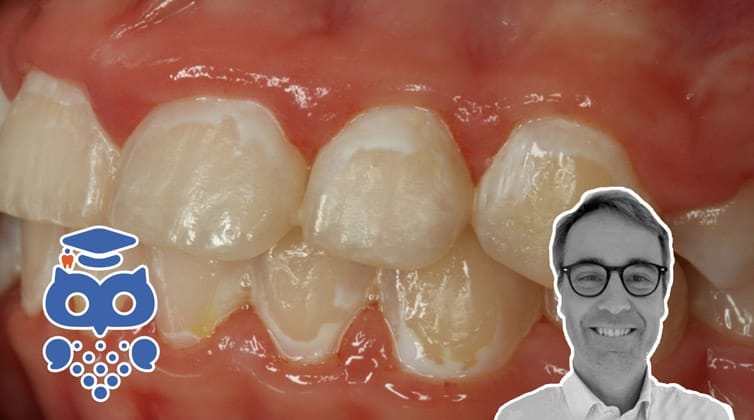

Cirka vart fjärde barn i Sverige behandlas med fast tandställning och upp till 50 % av dessa barn utvecklar så kallade ”White Spot Lesions” (WSL). Skadorna benämns WSL på grund av sitt oftast vitaktiga utseende, orsakat av ”urkalkning” av emaljen, och kan variera vad gäller antal drabbade ytor och utbredning på tanden (bild 1-2). Skadorna uppstår främst runt tandställningens fästen och kan upplevas som missprydande i och med att de ofta återfinns på framtänderna. Skadorna, som har en begränsad förmåga att spontant läka ut, kan liknas vid ett ärr som försämrar det slutgiltiga behandlingsresultatet.